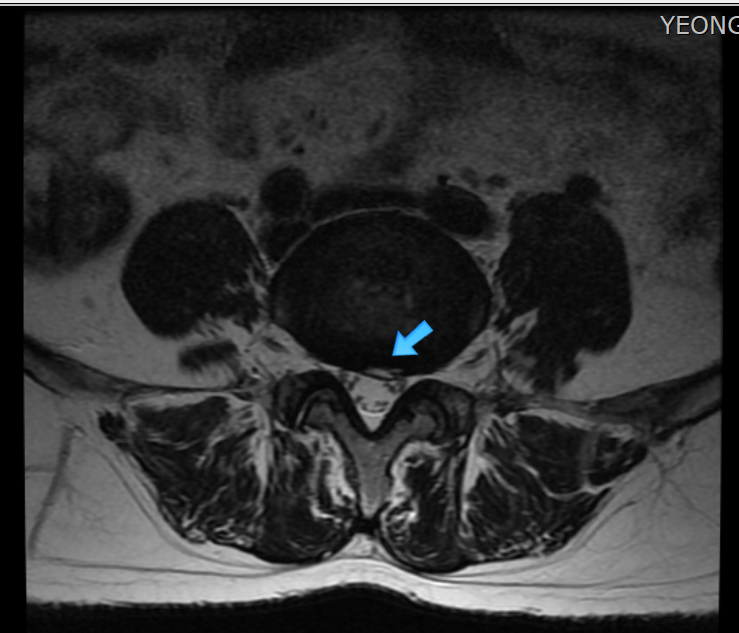

섬유륜파열은 굴곡, 신전, 측굴등의 관절가동범위를 제한하는 극심한 허리통증을 주증상으로 하지만 근력 약화, 하지의 방사통 또는 저리는 감각이 생길수도 있습니다. 허리에 부하되는 작은 압력도 잘 견디지 못하여 milgram test나 balsalva test 등에서 양성이 나오는 경우가 많으며 브릿지 동작등도 하기 힘들어 합니다. 특징적인 임상증상과 경과에 따라 진단하며, MRI 검사가 반드시 권고되는 것은 아니나 MRI 검사상에서 Annulus fibrosus의 열상(tear 또는 fissure)은 T2 강조영상과 조영증강영상에서 고신호강도(high siganl intensity zone)을 보입니다.

섬유륜파열 MRI 소견